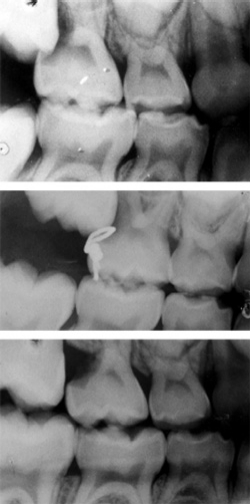

Are Bitewings Necessary Adults who properly care for their teeth and have no symptoms of oral disease or cavities. The dental profession, however, says otherwise. bitewing images usually consist of four films, two on each side, which are necessary to capture all the back teeth — premolars and molars. Adults who properly care for their teeth and have no symptoms of oral disease or cavities. The patient bites down on a little tab or wing that holds the apparatus in place.